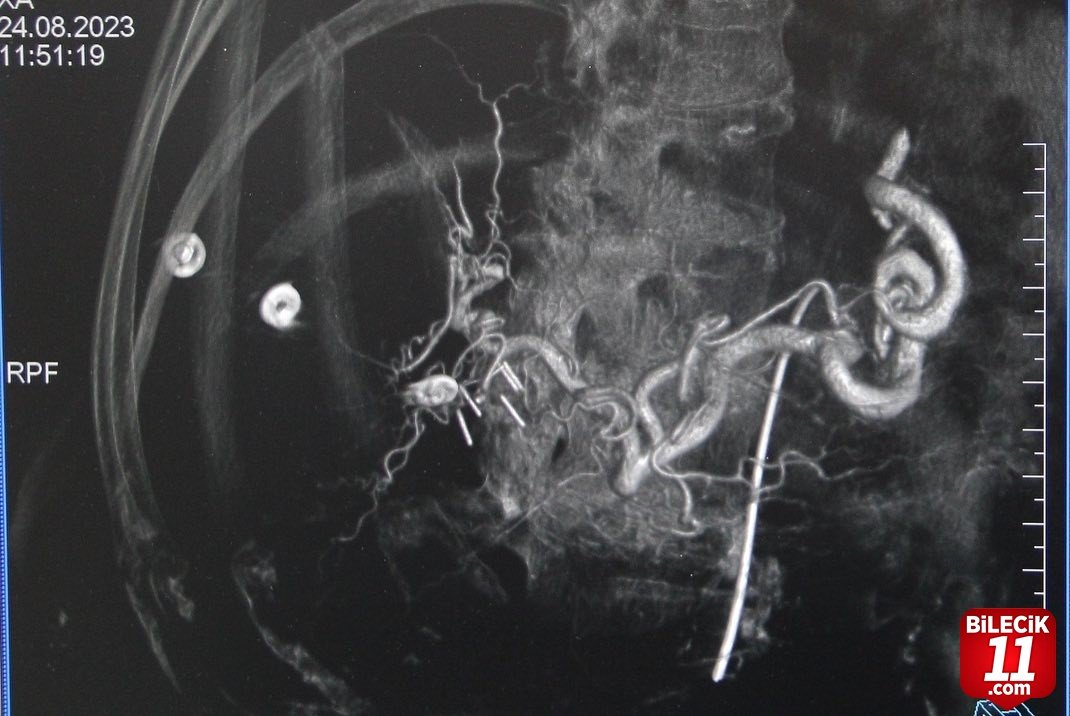

Kütahya Evliya Çelebi Eğitim ve Araştırma Hastanesi Girişimsel Radyoloji Hekimleri Prof. Dr. Mehmet Korkmaz ve Doç. Dr. Furkan Ertürk Urfalı tarafından, Kütahya’da ilk defa karaciğer tümörü olan üç hastaya Transarteriyel Radyoembolizasyon (TARE) işlemi gerçekleştirildi. Başarılı işlem sonrası Transarteriyel Radyoembolizasyon (TARE) hakkında bilgi veren Prof. Dr. Mehmet Korkmaz, ”Transarteriyel Radyoembolizasyon, karaciğer kanserlerini ve başka organ kanserlerinin karaciğere metastazlarını tedavi etmek için kullanılan bir tedavi yöntemidir. İçinde radyoaktif madde bulunan çok küçük boyuttaki kürelerin (mikroküre) direkt olarak kanser dokusu içine, kanser damarları yoluyla verilmesidir. Tümör ve metastazlarına yol açan hücrenin bulunduğu alana Nükleer Tıp uzmanlarımız tarafından hesaplanan dozlarla, radyoaktif madde içeren küçük küreciklerin (mikroküreler) enjekte edilmesidir. Radyoaktif madde olan itriyum-90 (Y90) mikroküreler, sağlıklı dokular korunarak, tam olarak tümör üzerine radyasyon uygulayarak etki ederler. Bu sayede çevre dokular zarar görmez. TARE tedavisi ile, karaciğerdeki tümörü küçülterek cerrahi tedaviye uygun hale gelmesini sağlar. Kanserli hücreleri öldürerek hastanın organ nakli için zaman kazanmasını sağlarken, organ nakli için başlangıçta uygun olmayan tümörü küçülterek nakil için imkan sağlar” dedi.

Prof. Dr. Korkmaz, ”TARE tedavisinde mikroküreler bir kan damarından geçer ve karaciğer tümörüne direkt ulaşır. Bu sayede radyoaktif madde, diğer radyasyon tedavilerinde olduğu gibi, kanser hücrelerine ulaşmak için vücudun sağlıklı kısımlarından geçmez. Doç. Dr. Furkan Ertürk Urfalı hocamız ve Nükleer Tıp Uzmanımız Dr. Elif Neslihan Akdemir’in destekleriyle birlikte hastanemizde ilk defa üç hastamıza, işlemi başarıyla gerçekleştirmiş bulunmaktayız. Bu işlemlerin yapılmasında emeği geçen ekibime ve bize bu imkanı sağlayan KSBÜ Rektörü Prof. Dr. Ahmet Tekin, İl Sağlık Müdürü Dr. Öğr. Üyesi Sertaş Erarslan ve Başhekim Dr. Öğr. Üyesi Serkan Telli’ye teşekkür ediyorum “ dedi. – İHA